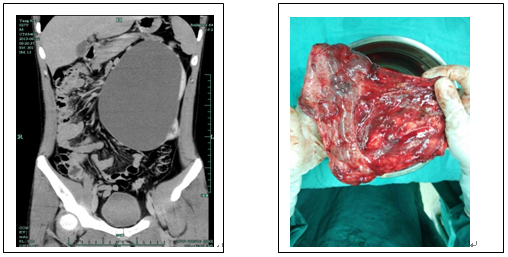

近日,我科收治了一位年轻患者,小伙子今年27岁,前几日一次无意中的检查发现左肾巨大积水,拿过CT片子一看,整个左肾犹如一只柚子占据着腹腔,旁边的肠子和胃被顶向了一边,肾皮质已经萎缩的只剩下了一层薄薄的皮。整个左肾的功能已经所剩无几,而且这种病肾易致感染,压迫周边的脏器,甚至很小的外力就有可能致其破裂,后果非常严重,需要及时得到处理。

经过精心的术前准备,决定实施微创腹腔镜下左侧积水肾切除术,手术由陈光耀、张逸两位医师操刀,在麻醉师及护士的熟练配合下顺利完成。整个过程通过腰间的三个小小的切口,找到病肾,光放出的积水就有1650ml,由于患者病程长,组织间粘连的厉害,通过细致耐心的分离,剥离出整个肾脏,术中出血不足20ml。患者的恢复也很理想,次日便能进食和下床走动,术后5天便出院回家。